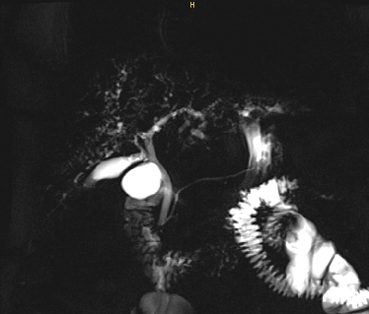

La paciente consultó nuevamente al servicio de urgencias por ictericia progresiva, se realizaron paraclínicos que reportaron alteración del perfil hepático a favor de ser colestásico (tabla 1), y ecografía de hígado y vías biliares con cambios de adenomiomatosis vesicular, descartando dilatación de la vía biliar. Se aclararon hallazgos con resonancia simple y contrastada de abdomen que evidenció patrón de colangitis esclerosante con vía biliar desestructurada de manera difusa (figuras 1 y2).

El diagnóstico de colangitis esclerosante secundaria se realiza por colangiopancrea-tografía retrógrada endoscópica (CPRE) o colangiorresonancia. Estos métodos logran identificar estenosis y dilataciones difusas de los conductos biliares intrahepáticos, y defectos de llenado con cilindros biliares [11]. En el presente caso, la resonancia simple y contrastada de abdomen evidenció el patrón de colangitis esclerosante con una vía biliar desestructurada de manera difusa, con microcálculos y barro biliar. Previo al desarrollo de estas complicaciones, la paciente tenía pruebas de función hepática con una alteración leve, y la estructura de la vía biliar era normal. Además, no tenía criterios para una colangitis esclerosante primaria, y se descartaron de manera racional otras causas secundarias.